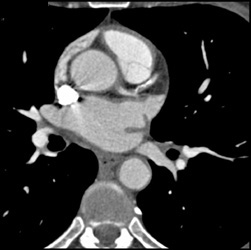

Diagnosis

Normal RCA